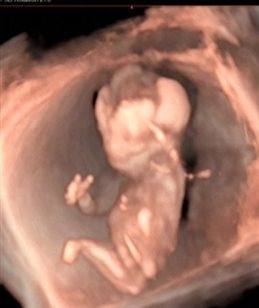

早孕期胎儿颈项透明层(nuchal translusancy thickness,NT)实际上就是宝宝的颈后透明层检查。胎儿畸形与NT值增厚关系密切,当NT的厚度超过正常范围,且数值越大,胎儿出生后患病的几率也越大。除了胎儿出生后,可能会患有染色体、心脏等问题外,还要考虑是否患有唐氏综合征,并要做好进一步检查的准备。

NT检查在孕11~14周做,过了14周,过多的液体可能就会被宝宝正在发育的淋巴系统吸收,准确率就会大大降低。